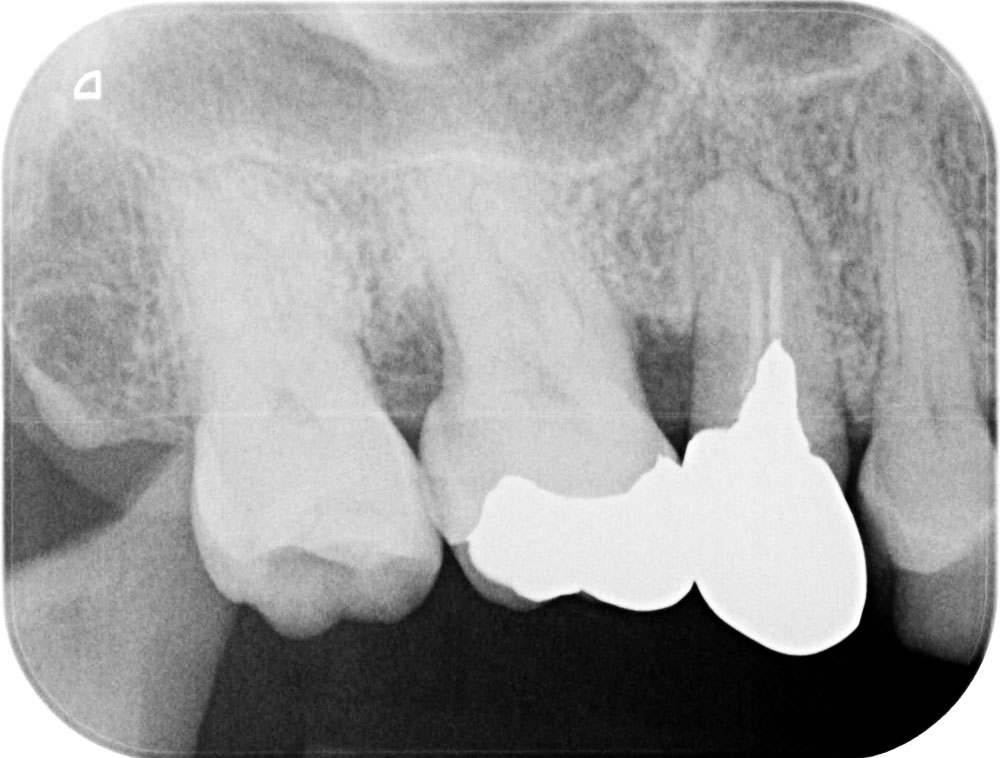

歯周再生治療前

歯周再生治療後

患者さんは40代の女性で、歯がグラグラで噛めないので噛めるようしたいと恵比寿・広尾歯科に来院されました。お口のなかを拝見すると歯周病が進行し特に奥歯の歯周ポケットが深くなり、歯を支える顎の骨が溶けている状況でした。歯ブラシで磨きにくいため汚れが溜まりやすいだけでなく、奥歯は噛み合わせの力が強く加わり歯周病の悪化しやすい歯です。この患者さんも以前、保険の銀歯で治療されていましたが、年々歯がグラグラ(動揺)して噛めないとご来院されました。

歯周病認定医でもある院長 前島による歯周病診断、歯周基本治療のうえで、エナメルマトリクス蛋白(EMD/エムドゲイン)による歯周病再生療法により失われた顎の歯を支える骨を再生します。このエナメルマトリクス蛋白は、幼若ブタの歯胚から抽出・精製したもので、このタンパク質により歯が生えるメカニズムを応用して失われた骨の再生を促します。今回は基本歯周治療と歯周再生療法による歯周病治療をおこないました。